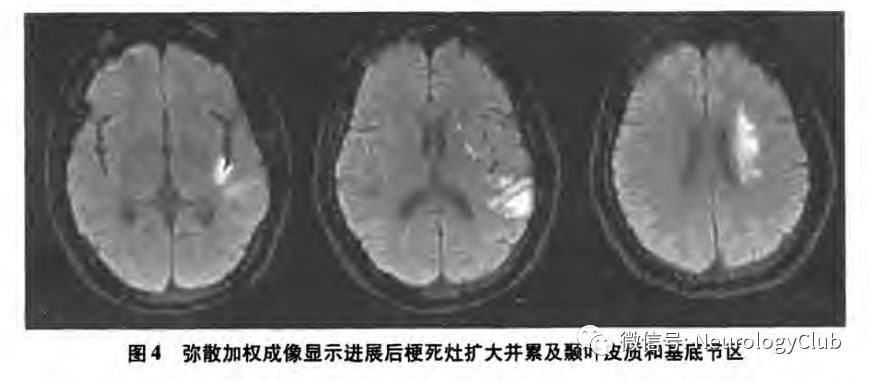

另有研究表明,分水岭梗死往往预示着END的发生,尤其是内分水岭梗死后者多表现为多发性梗死,且通常伴有严重的大动脉狭窄,血流动力学障碍可能是其最主要的发病机制。Kim等报道了12例伴有颅内动脉重度狭窄的小卒中患者,根据梗死部位和分布特点,将急性期DWI显示的梗死灶分为4种模式:内分水岭梗死、皮质分水岭梗死、皮质支梗死和深穿支动脉梗死,结果显示,END更多见于内分水岭梗死。随后的一项研究共纳入了95例伴有大脑中动脉或基底动脉中到重度狭窄的小卒中或短暂性脑缺血发作(transient ischemic attack,TIA)患者,END发生率为14.7%,logistic回归分析显示,分水岭梗死是END的独立预测因素(P=0.004)。虽然分水岭梗死的病理生理学机制仍存在争议,但一般认为低灌注与微栓子共同导致了分水岭梗死,低灌注导致的微栓子清除障碍在分水岭区更为多见,易出现卒中进展。因此,早期神经影像学发现,尤其在DWI显示病灶分布散在,可能有助于预测END的发生(图2-4)。